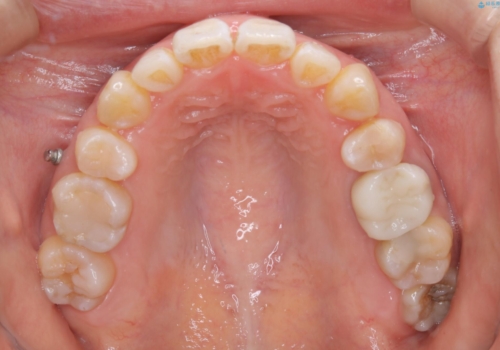

- 全体的に着色が付いているのが気になるとのことで来院されました。

PMTC60分コースを行いました。

着色がかなり頑固なため、エアフローも使い着色を除去していきました。

下の前歯にはかなり多くの歯石が付いており、デンタルフロスでもう少し防げるため、使用法や頻度を確認しました。